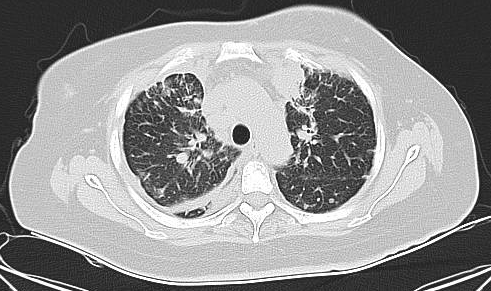

胸部CT(2023-5基线):双肺见多发结节(较大者约7mm×7mm),考虑转移;另见多发类结节影(较大者约27mm×26mm,内可疑支气管气象),需鉴别转移或实变。双肺轴心间质增厚,伴多发小叶间隔增厚,符合癌性淋巴管炎表现。双侧胸膜增厚、胸腔积液,考虑转移。双侧锁骨上区、纵隔多组、双侧内乳区、左腋下及腹膜后见多发肿大淋巴结(较大者约20mm×11mm),考虑转移。胸廓骨多发转移;T2、T12椎体压缩骨折。左乳结节约34mm×19mm,考虑恶性。

治疗仅8周后,复查胸CT、腹盆CT、头MR、肿瘤标志物,评效结果为缩小的SD,肿瘤标志物下降,肝功能恢复正常。基线27mm的肺部病灶在持续治疗中不断缩小,至2025年4月CT复查完全消失,并维持至今。脑转移灶5mm缩小至2-3mm。